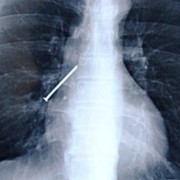

Можеби понекогаш се чувствувате виновно заради обилниот ручек што сте го изеле, но кога ќе видите што ставиле овие луѓе во својот стомак, ќе сфатите дека вие немате причина да се грижите. Барем не сте изеле батерии. Иако можеби имаат помалку калории, попрво би јаделе вкусни слатки со многу масти отколку киселински раствор. Луѓето имаат изедено некои многу чудни нешта…